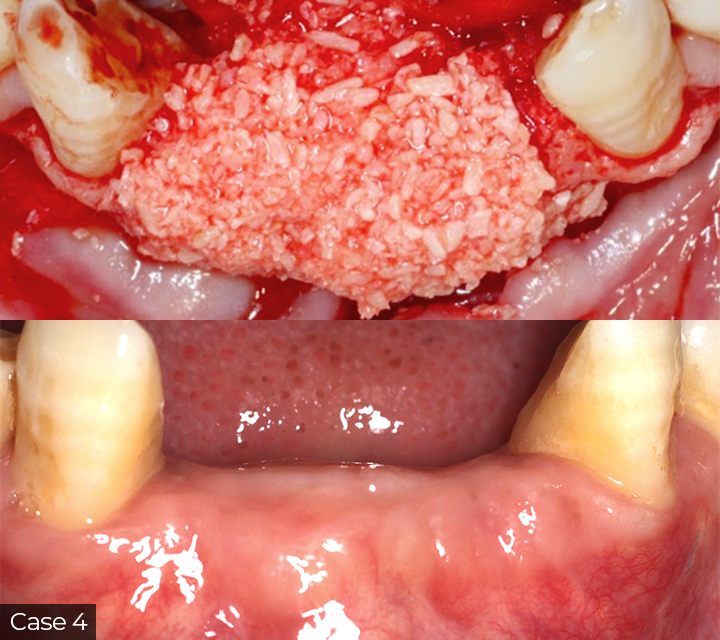

This course offers a focused overview of key surgical techniques in implant and periodontal treatment. Topics include guided bone regeneration principles, biomaterial selection, autogenous bone harvesting, and management of compromised sockets. Emphasis will be placed on soft tissue handling, including flap advancement, the LASSO suturing technique, and free gingival grafts. Participants will also learn how to manage complications effectively.

A hands-on workshop will provide practical experience in suturing and grafting techniques, helping clinicians apply these skills confidently in clinical practice.

Director’s Clinical Cases

This course offers a focused overview of key surgical techniques in implant and periodontal treatment. Topics include guided bone regeneration principles, biomaterial selection, autogenous bone harvesting, and management of compromised sockets. Emphasis will be placed on soft tissue handling, including flap advancement, the LASSO suturing technique, and free gingival grafts. Participants will also learn how to manage complications effectively.

A hands-on workshop will provide practical experience in suturing and grafting techniques, helping clinicians apply these skills confidently in clinical practice.

Director’s Clinical Cases